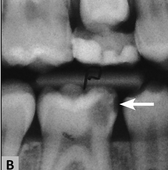

aprezentowany powyżej problem jest dość złożony. Podejmując się leczenia pierwszego zęba trzonowego u sześcioletniej osoby należy zdawać sobie sprawę z faktu, że korzenie zęba nie są w pełni ukształtowane i z całą pewnością kanał nie ma kształtu stożka zwężającego się w kierunku wierzchołka, ściany korzeniowe są cienkie, a otwory wierzchołkowe bardzo szerokie. Stąd należy zachować szczególną ostrożność podczas opracowywania głębokich ubytków w zębach z niezakończonym rozwojem i dążyć do zachowania żywej miazgi unikając tym samym bardzo trudnego do wykonania i nieprzewidywalnego leczenia endodontycznego. Ponieważ rozpoznano klinicznie próchnicę głęboką należało wykonać zdjęcie rentgenowskie i ocenić głębokość ubytku. Europejskie Towarzystwo Endodontyczne wyróżnia 2 typy próchnicy głębokiej, tj.: próchnicę głęboka (deep caries, ryc. 1) i próchnicę bardzo głęboką (extremely deep caries, ryc. 2). W przypadku próchnicy głębokiej na zdjęciu rentgenowskim widoczna jest warstwa zębiny oddzielająca dno ubytku od sklepienia komory o grubości 1/4 -1/3 szerokości (grubości całej zębiny) (ryc. 1 B), podczas gdy w próchnicy bardzo głębokiej proces próchnicowy niszczy zębinę na całej jej grubości (na zdjęciu nie widać zmineralizowanej warstwy zębiny oddzielającej dno ubytku od komory miazgi) (ryc. 2 B). W prezentowanym przypadku na pewno nie byłoby problemu z postawieniem diagnozy (głęboka vs. bardzo głęboka) ze względu na lokalizację ubytku na powierzchni zwarciowej (dobra widoczność ubytku zdjęciu rentgenowskim w związku z nienakładaniem się na niego zdrowych struktur, co z kolei ma miejsce np. w ubytkach klasy I zlokalizowanych na powierzchni policzkowej zębów trzonowych i tu trudno ustalić rozpoznanie na podstawie radiogramu). Ustalenie prawidłowego rozpoznania jest dość istotne, gdyż nieco inne jest postępowanie w przypadku, gdy mamy do czynienia z próchnicą głęboką niż gdy jest to próchnica bardzo głęboka. W obu przypadkach należy usunąć próchnicę ze ścian ubytku, natomiast z dna próchnicową zębiny należy usunąć selektywnie: w przypadku próchnicy głębokiej do tzw. zbitej zębiny, a w przypadku próchnicy bardzo głębokiej nawet pozostawiając na dnie miękką zębinę (w tabeli 1 dla przypomnienia typy zębin). W pierwszym przypadku postępowanie polega na zastosowaniu na dno (w tym na pozostawioną na dnie zdemineralizowaną zębinę) materiału bioaktywnego (najlepiej cementu krzemowo-wapniowego względnie c. szkło-jonomerowego lub preparatu wodorotlenkowo-wapniowego), a następnie po założeniu ew. podkładu na wypełnieniu ostatecznym ubytku (ryc. 3). W drugim przypadku, gdy pozostawiamy miękką zębinę ubytek należy wypełnić czasowo na 6-12 miesięcy (leczenie dwuetapowe). Dno, tak jak w pierwszym przypadku najlepiej szczelnie przykryć cementem bioaktywnym na bazie krzemianu wapnia (ryc. 4). Takie postępowanie w próchnicy głębokiej, czyli selektywne usunięcie próchnicowej zębiny dokomorowej obarczone jest znacznie mniejszym ryzykiem powikłań ze strony miazgi aniżeli nieselektywne, czyli doszczętne usunięcie zębiny próchnicowej do zębiny twardej (zdrowej). Co więcej w przypadku próchnicy bardzo głębokiej próba usunięcia zębiny próchnicowej nawet do tzw. zębiny zbitej skutkuje odsłonięciem miazgi. W przypadku dwuetapowego leczenia próchnicy należy po upływie określonego czasu (6-12 miesięcy, a w przypadku zębów niedojrzałych najbezpieczniej do momentu zakończenia rozwoju korzenia) usunąć wypełnienie czasowe i sprawdzić, czy miękka zębina uległa mineralizacji. Jeśli zębina uległa mineralizacji, to nie ma potrzeby tzw. „doczyszczenia” ubytku, choć w wielu przypadkach okazuje się konieczna dodatkowa preparacja.

Ryc. 2. Próchnica bardzo głęboka. A. Schemat, B. Zdjęcie rentgenowskie